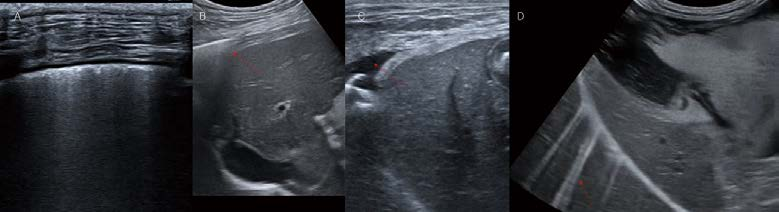

먼저 흉부초음파(폐초음파)에서 실수하기 쉽거나, 꼭 고려해야 하는 부분이 몇 가지 있습니다. 피하 내 기종, 미만성의 피부 질환, 비만한 환자 등에서 폐가 제대로 스캔되지 않았는데, B line으로 오진하는 경우가 많습니다. 늑골과 늑골 사이에서 lung sliding을 관찰하면서 pleural line, lung periphery, A line 등을 잘 확인해서 판독 가능 여부를 명확히 해야 합니다. 또한 미약한 B line 1개, 짧은 comet tail artifact(B line은 흉막에서 시작해서 수직으로 아래로 뻗는 음영입니다. lung sliding과 함께 움직이며, 한 개의 늑간 사이에 적어도 3개 이상 나타나야 하고, 화면의 끝까지 fading 없이 이어지는 고에코성 라인이어야 임상적 의미가 있다고 보고 있습니다) 등을 병적 상태로 과대 평가하지 않도록 주의해야 합니다(D). 호흡곤란 환자에서 aerophagia로 인해 stomach가 공기로 확장되는 경우가 많은데, 이 때, 확장된 위벽은 얇아져 마치 pleural line처럼 linear하게 보이게 됩니다. 왼쪽 후엽 스캔 시 위 내 공기를 왼쪽 후엽의 confluent B line으로 오진하는 경우도 많습니다.

(A). 폐초음파에서 양쪽 caudodorsal, perihilar, middle, cranial lung field view 모두 8 views 뿐만 아니라 diaphragmatic-hepatic view도 매우 중요합니다. Diaphragmatic hepatic view에서 정상적으로 관찰될 수 있는 curtain sign(B)을 인지하고, 이 부위의 변화 소견은 costophrenic recess, peripheral lung base와 관련된 pulmonary pathology를 발견하는데 유용합니다(C, pleural effusion).